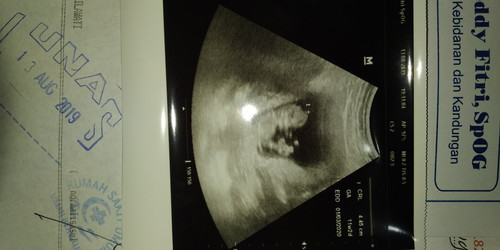

ini adik laki2 atau perempuan ya

Ini adik laki 2atau purempuanya

Belum bisa dliat Masih terlalu muda

Blom kliatan bun.. sabar

11w belom keliatan